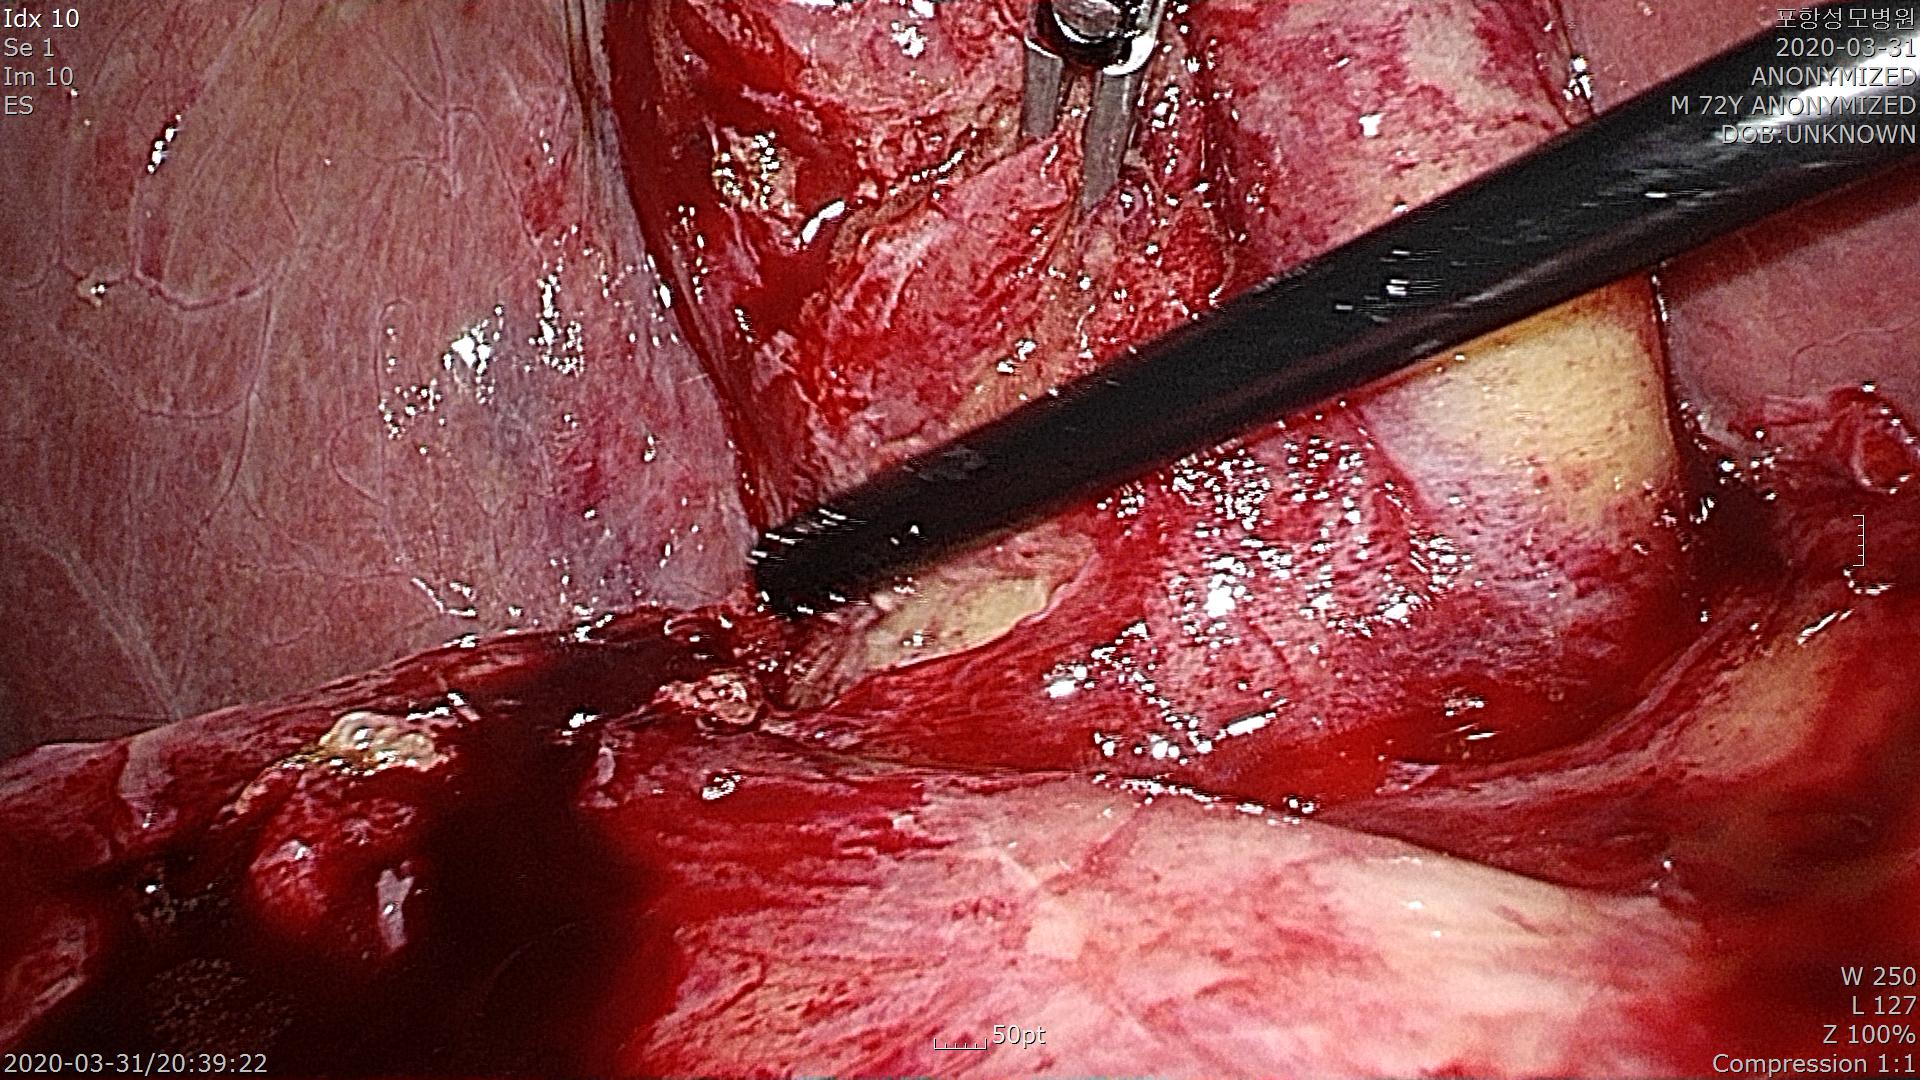

담낭에 염증이 심하고 썩어 들어가 천공(구멍)이 되기 직전입니다.

담낭이 부풀어 올라 복강경 포셉으로 잡기 어려워 구멍을 내고 담낭내의 담즙을 흡입하여 담낭을 잡기 좋게 만듭니다.

총담관으로 들어가는 담낭관을 확인하기 위해 박리를 시작합니다.

염증이 심한 조직은 출혈도 많고 쉽게 부서지기 때문에 집중해서 수술해야 합니다.